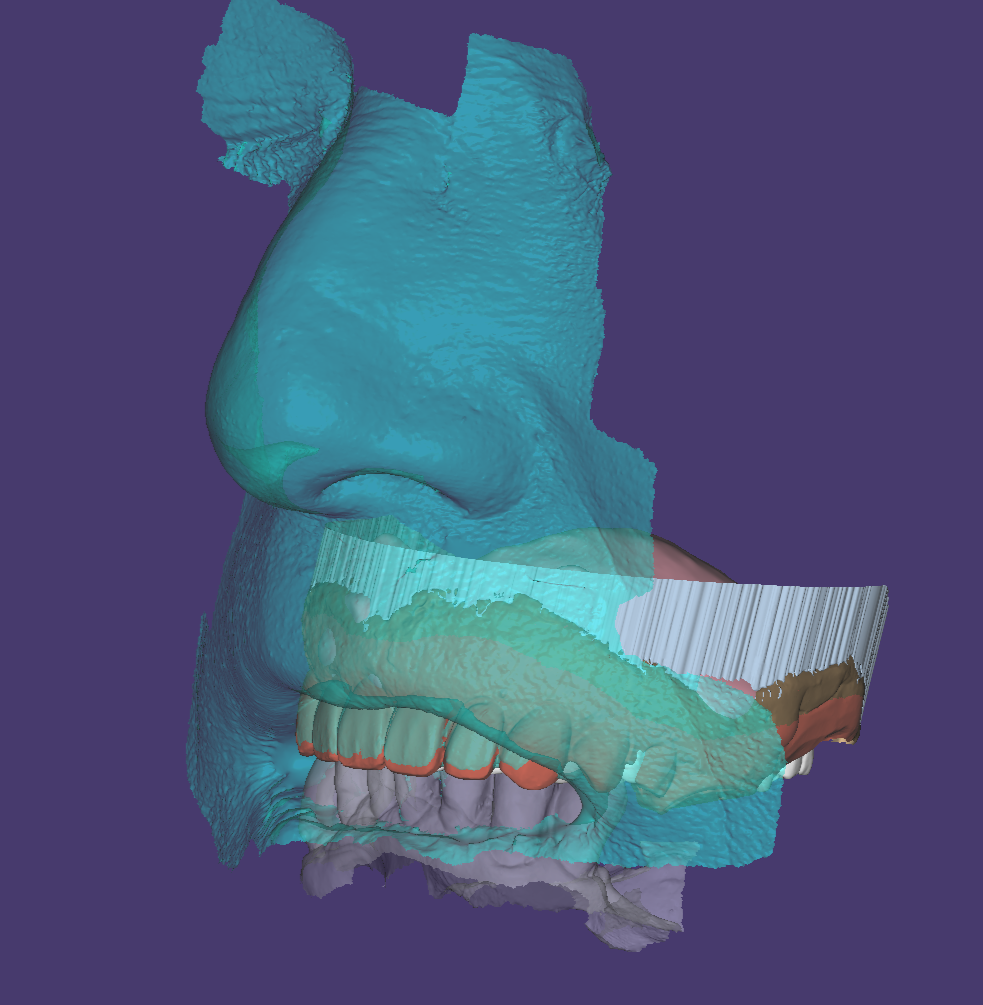

他院で入れ歯を作ったけど あまり使わなかったことで、前歯が折れてグラグラな状態でしたが、デジタルでの型取りにて、製作開始。

2回目

連結されている前歯を切断するとともに、折れた根の抜歯を行い、その後デジタルデンチャーを装着し機能回復を開始しました。